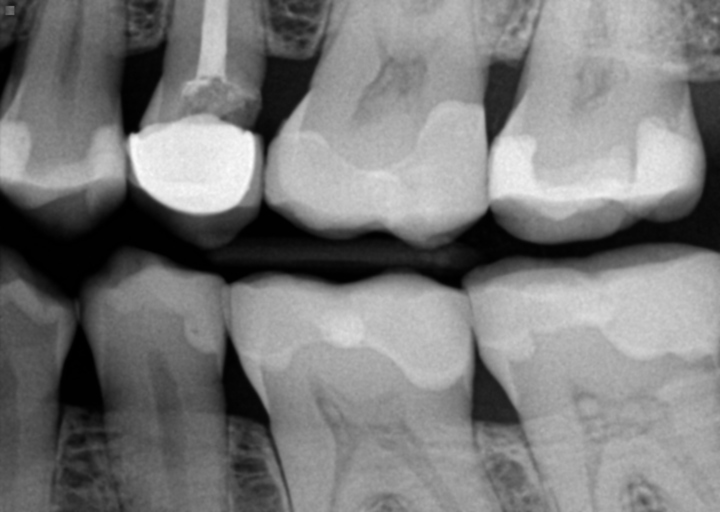

About 2 years ago, while I was in college and I was on Christmas break 2008, I had a root canal procedure in the molar identified as #15. After the procedure, my dentist measured the tooth for the crown and then placed a temporary crown over the shaved tooth. I was supposed to receive the permanent crown, in a month when I return home on another break but the permanent one fell out. The dentist had to shave the tooth down more & also replace two orange rubbery fillings that came out. Two months later, I went back to my dentist to have the permanent crown fitted. When the dentist attempted to put the crown on, it didn\'t fit properly. Two months later (it\'s now summer time, I\'ve graduated from college, and now I am home), I go to the dentist to have the new permanent crown placed. The process is finally completed. Fast Forward to now, 1 &1/2 years later. M In the past three weeks, I experienced a massive amount of pain in the molar where the canal was performed. It started as a a constant throbbing pain all over the head and even in my chest. I had a fever the first day this occurred. Some days the pain goes away but still hurts when pressured is applied. Some days I experience the throbbing pain again. I can\'t eat on those days or even speak. I take advil but it doesn\'t always work. A few nights I have been unable to sleep. It seem laying down only makes the pain worse. I went to another Dentist at NYU School of Dentistry. The students and the professor say an infection is in the canal. I went back to my Dentist so that he too could take an x-ray. The infection was there when he first performed the root canal. But other x-rays show the infection remained even after the root canal was performed. I’m pretty sure it was supposed to be removed during the procedure. I am also pretty sure he was aware it remained but did nothing about it because he wanted me to continue to come so that he could make money off my insurance. When I returned to him yesterday to get xrays, he gave me a prescription for antibiotics & removed my crown so that it will relieve the pressure (“your infection presses down on the tooth as your bottom teeth force the teeth up.”) The crown is damamged and cannot be placed back on. I now have no insurance. I have two deep cavities that must be filled. NYU will charge me $700 to retreat the canal. I have no clue how much the new crown will cost. The fillings at NYU may cost $120 each. (Also, one of the cavities was already filled by my dentist in 2009 and fell out during Summer 2010). I don’t trust my dentist. Also we will probably charge way more. I asked him several times for an estimate concerning the fillings and he consistently attempted to beat around the bush. He also said he may need to perform a root canal on the tooth where the filling came out. NYU said the the cavity is deep but a root canal is not necessary. I have decided to have both fillings done. Now that I have antibiotics, I am considering just having the tooth measured for a new crown without having the root canal procedure redone. What should I do?

I'm sorry you are experiencing such a traumatic time with this tooth. First, after the root canal is performed a permanent crown should be placed as soon as possible to keep the tooth clean and sealed away from as much bacteria as possible. Unfortunately, your crown didn't fit several times and you were placed repeatedly in temporary crowns that are not completely sealed and allow small amount of bacteria to attack the tooth. The small orange rubbery pieces (gutta percha) that were replaced should have never come out after the root canal was sealed, unless the tooth was isolated and retreated. When those are removed bacteria can access those canals and reinfect your tooth. This may or may not be the reason you currently need Retreatment. Antibiotics will help your body fight the infection for a short period of time, however it will come back. It is not advisable to have a new crown fitted if both dentists say the tooth needs to be retreated. When having the retreatment performed, see an endodontist with an operating microscope for the best results. Definitely have the two fillings placed prior to them insulting the nerve and needing further treatment such as root canal therapy. It is best to avoid this at all costs.